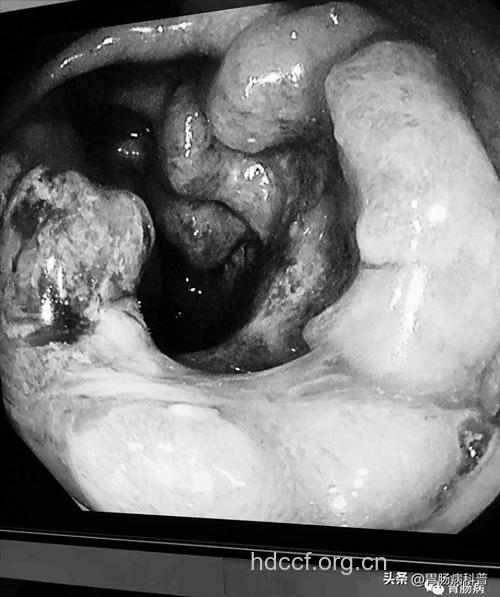

无症状是大肠癌的隐身衣。大肠癌系自大肠粘膜上皮起源的恶性肿瘤称为大肠癌。是最常见的消化道恶性肿瘤之一。临床常见血便或粘液脓血便,大便形状或习惯发生改变,腹痛,腹部包块等。根据其发生部位不同,其临床表现常各有其特殊性。大肠癌具有起病隐匿,早期常无明显的临床表现,病情发展较慢,远期疗效优于其他消化道恶性肿瘤,预后相对较好;但大肠癌发病率高并有连年上升趋势。

& 大肠癌早期没有明显症状,所以,不易引起人们的警惕。大肠癌的常见症状是腹部包块,为癌肿增大后形成;典型的腹泻与便秘交替进行,并有里急后重感,肛门下坠感,便意频繁,似欲腹泻,但每次不过便些粘液,日便次可达20至30次;可有脓血粘液便,或大量便血;可出现肠梗阻症状,因癌肿进一步增大,使肠管变得狭窄或全部堵塞而致。

& 晚期可出现贫血、腹水、纳食等。一旦出现明显的症状,疾病多已达到中晚期。病人的手术效果与疾病阶段有着密切的关系。早期癌手术后,5年生存率可高达90%以上;而晚期癌即使手术,5年生存率也极低。由此可见,早期发现、早期诊断、早期治疗已成为治疗大肠癌的关键。